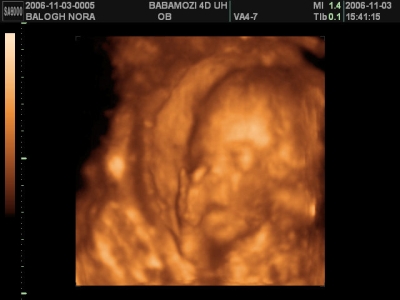

Egyébként egy vizsgálat úgy kezdődik, hogy megkérdezi, hogy "Hogy vagyunk, minden rendben?" Ha igen, akkor UH, kép. És amikor leülsz az asztalhoz, elmondja, mit írt a kiskönyvbe. Mik a pontos adatok. 100szor UH-zott, mégis mindig szól, hogy "jaj, ez most hideg lesz" meg ilyesmi. Én úgy gondolom, hogy egy probléma mentes terhesség során nem is kell, hogy tovább tartson egy vizsgálat.